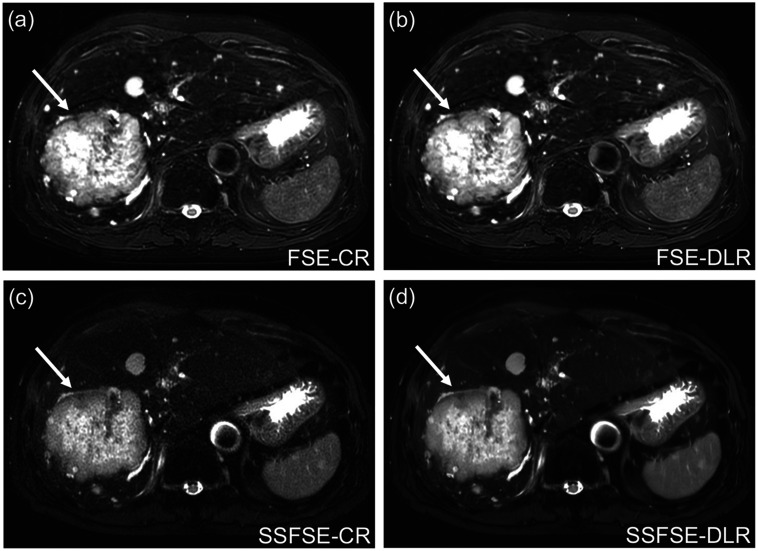

Methods: Respiratory-triggered fat-suppressed liver T2-weighted MRI was obtained with the FSE and SSFSE sequences at the same spatial resolution in 55 patients. Conventional reconstruction (CR) and DLR were applied to each sequence, and the SNR and liver-to-lesion contrast were measured on FSE-CR, FSE-DLR, SSFSE-CR, and SSFSE-DLR images. Image quality was independently assessed by three radiologists. The results of the qualitative and quantitative analyses were compared among the four types of images using repeated-measures analysis of variance or Friedman's test for normally and non-normally distributed data, respectively, and a visual grading characteristics (VGC) analysis was performed to evaluate the image quality improvement by DLR on the FSE and SSFSE sequences.

Results: The liver SNR was lowest on SSFSE-CR and highest on FSE-DLR and SSFSE-DLR (P < 0.01). The liver-to-lesion contrast did not differ significantly among the four types of images. Qualitatively, noise scores were worst on SSFSE-CR but best on SSFSE-DLR because DLR significantly reduced noise (P < 0.01). In contrast, artifact scores were worst both on FSE-CR and FSE-DLR (P < 0.01) because DLR did not reduce the artifacts. Lesion conspicuity was significantly improved by DLR compared with CR in the SSFSE (P < 0.01) but not in FSE sequences for all readers. Overall image quality was significantly improved by DLR compared with CR for all readers in the SSFSE (P < 0.01) but only one reader in the FSE (P < 0.01). The mean area under the VGC curve values for the FSE-DLR and SSFSE-DLR sequences were 0.65 and 0.94, respectively.

Conclusion: In liver T2-weighted MRI, DLR produced more marked improvements in image quality in SSFSE than in FSE.